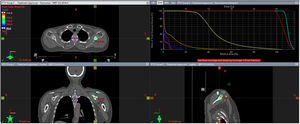

Tratamiento locorregional. Se trata del tratamiento con radioterapia adyuvante en una paciente que tras recibir 6 meses de tratamiento sistémico y presentar una respuesta parcial es intervenida de una mastectomía total simple y una linfadenectomía, seguida de radioterapia adyuvante sobre la pared costal y las cadenas ganglionares axilar y supraclavicular homolateral (niveles axilares I-IV), con un esquema de hipofraccionamiento moderado (40,05 Gy en 15 fracciones). Corte de la planificación en axial, coronal y sagital. Adicionalmente el histograma dosis/volumen de la dosimetría.